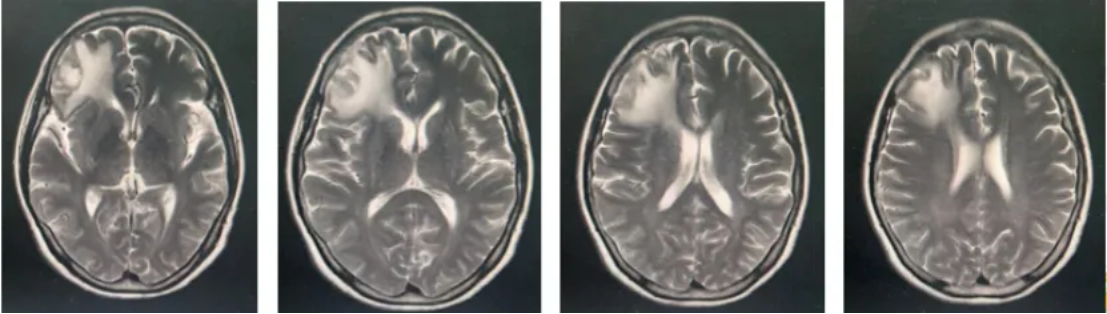

不良反应及疗效评价:患者未出现白细胞减少及肝肾功能异常,无明显消化道反应。3个疗程后,疗效评估为PR(图2)。

图2:影像结果

病情评估:新冠病毒感染重症肺炎,出现呼吸衰竭,治疗3周后残留肺间质纤维化,停药1个月后,患者疾病仍稳定,继续予以第4疗程化疗(图3)。

图3:影像结果